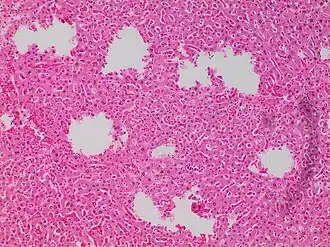

In microscopy, an artifact is an apparent structural detail that is caused by the processing of the specimen and is thus not a legitimate feature of the specimen. In light microscopy, artifacts may be produced by air bubbles trapped under the slide's cover slip.[1]

In electron microscopy, distortions may be produced in the drying out of the specimen. Staining can cause the appearance of solid chemical deposits that may be seen as structures inside the cell. Different techniques including freeze-fracturing and cell fractionation may be used to overcome the problems of artifacts.[1]